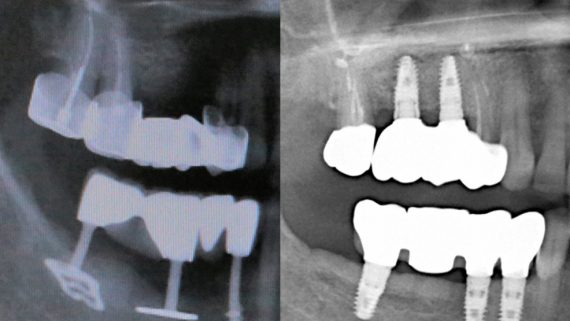

Я постараюсь показать вам, почему из этого:

получается это:

с минимальными затратами сил, нервов и денег. Этого не объяснить в рамках видеофильма или показа отдельного клинического случая. Это невозможно прочувствовать на челюсти барана или корке апельсина. В конце концов, если кто-то из докторов пожелает увидеть это «вживую», так сказать, с эффектом полного присутствия — очень скоро мы возобновим Индивидуальный Практический Курс и… добро пожаловать!